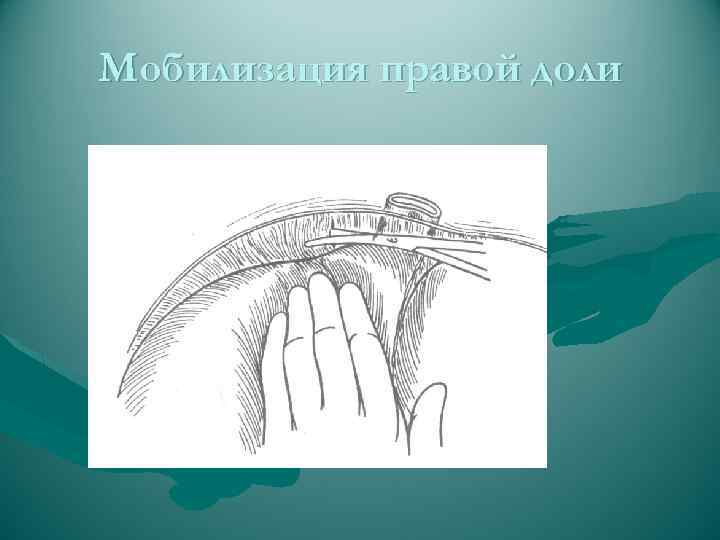

Мобилизация правой доли

Мобилизация правой доли